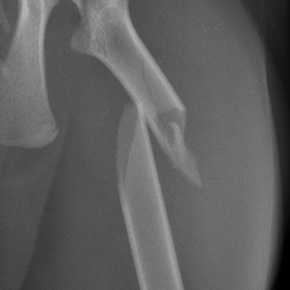

Orthopädie / Gelenkoperationen / Kreuzbandriß

Hüftgelenkoperationen